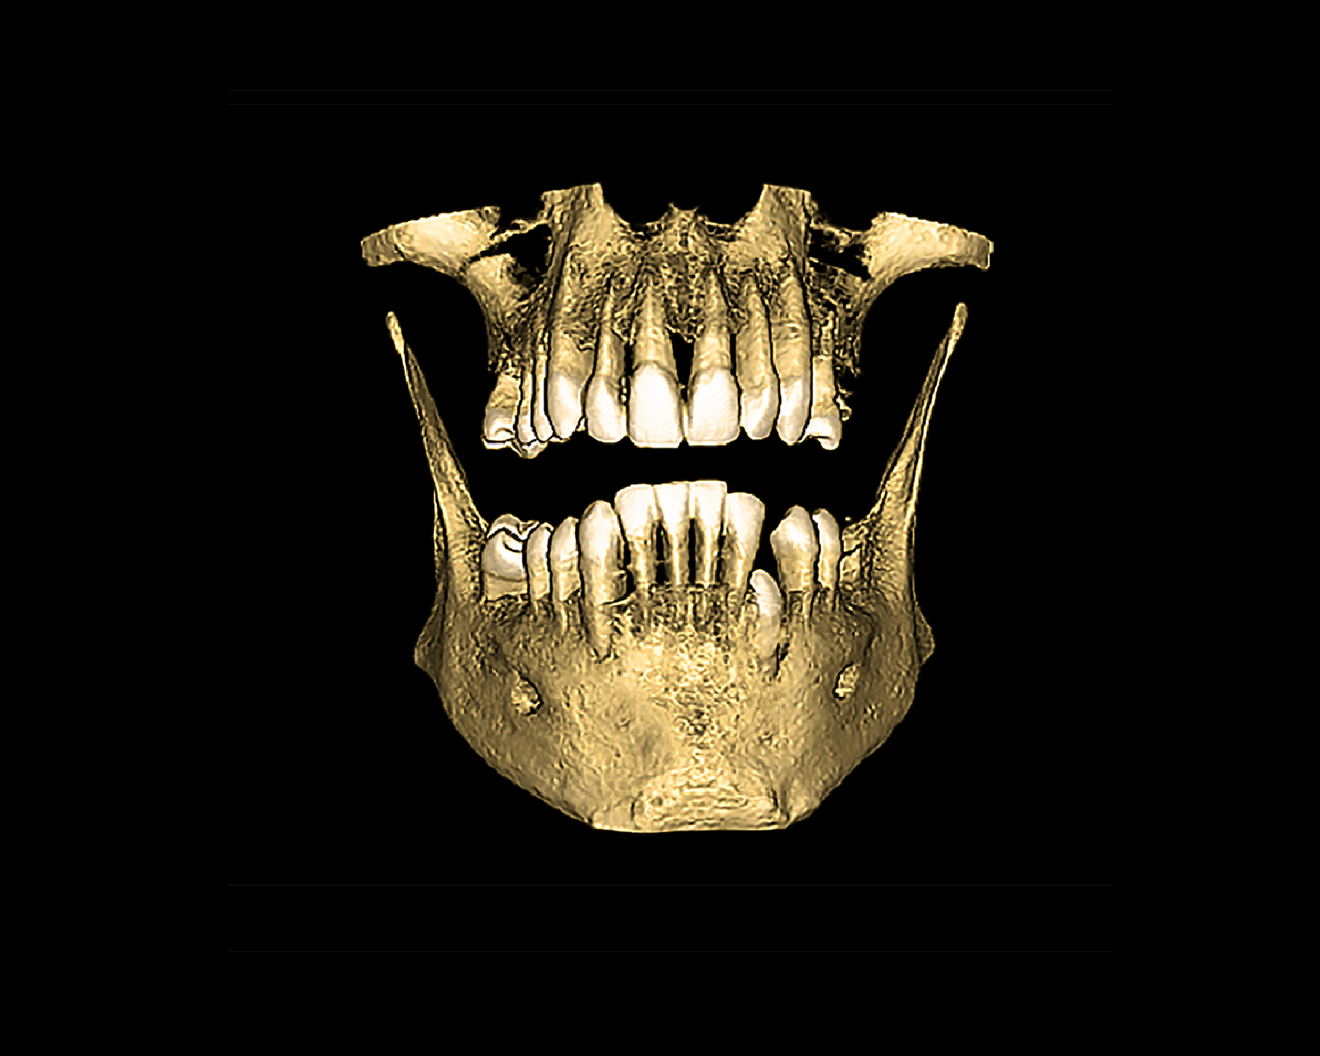

The following case exhibits the features and benefits of utilising Grammetry in combination with innovative screw technology. The 63-year-old male patient with a non-contributory medical history presented with failing dentition in both arches. Diagnostic records were collected, including full-mouth digital radiographs (RVG 6200, Carestream Dental; Fig. 11a), intra-oral scans (Medit i700 wireless; Figs. 11b & c), a large field of view CBCT scan (Carestream 9600; Fig. 11d), and intra-oral and extra-oral photographs (Fig. 11e). The mandible contained an impacted canine as well as several mobile and painful teeth. The maxilla was in a similar condition, having deteriorating, painfully mobile teeth, as well as extensive caries. While the bone loss was significant in the mandible, the vertical dimension of occlusion (VDO) allowed for both arches to be treated with an FP-1 prosthesis.

Fig. 11b: CBCT scan for diagnosis and treatment planning.